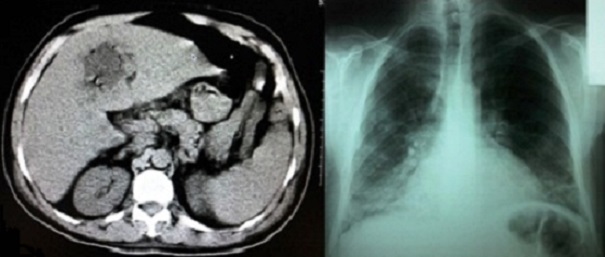

L'abcès hépatique amibien se définit comme une collection suppurée située au sein du parenchyme hépatique, il est secondaire à l'amibiase colique par Entamoeba histolytica histolytica dont la dissémination se fait par la circulation portale. Il peut être révélé par des signes respiratoires. Son diagnostic repose sur l'imagerie et la sérologie. Le traitement est médical à l'aide du métronidazole, l'évacuation de l'abcès peut être chirurgicale ou percutanée guidée par échographie ou par tomodensitométrie. Nous rapportons un cas d'un patient âgé de 44 ans, ayant présenté il y'a 45 jours une diarrhée mal traitée, admis aux urgences pour dyspnée, toux et fièvre évoluant depuis 7 jours. Le bilan initial avait conclu à un sépsis à point de départ pulmonaire devant la présence d'un syndrome infectieux clinique, une hyperleucocytose à 19500/mm3, une CRP à 183mg/l, et une image en faveur d'un foyer pulmonaire basal bilatéral. Une antibiothérapie par ceftriaxone 2g/24h a été administrée, mais devant l'aggravation de tableau clinique une TDM abdominale a été réalisée et a mis en évidence une masse hépatique du segment IV de densité liquidienne, bien limitée, non rehaussée après injection du produit de contraste iodé, cette masse renferme des bulles aériennes permettant d'évoquer le diagnostic d'abcès hépatique. Devant ce tableau, le métronidazole 500 mg/08h a été associé et le drainage chirurgical a été réalisé ramenant un liquide brun chocolat dont l'étude parasitologique était négative. La sérologie pour Entamoeba histolytica histolytica était positive. Le patient est décédé suite à une hypoxie réfractaire sur syndrome de détresse respiratoire aiguë.